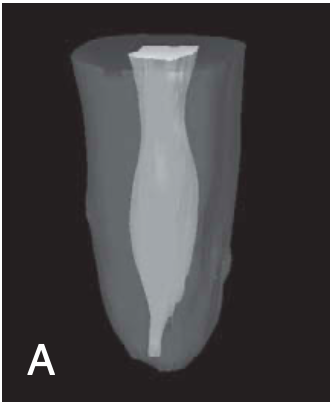

C-shaped roots and canals

most common in MN 2nd molars

also reported in MN 1st molars, MX 1st & 2nd molars, MN 1st premolars

can vary along the root depth so that the appearance of the orifices may not be good predictors of the actual canal anatomy

2 basic types of C-shaped roots and canals

single ribbonlike canal — from orifice to apex (rare)

multiple distinct canals — below the C-shaped orifice (more common)

feature of a root canal obturation

ribbonlike canal space with an arc of 180 degrees or more